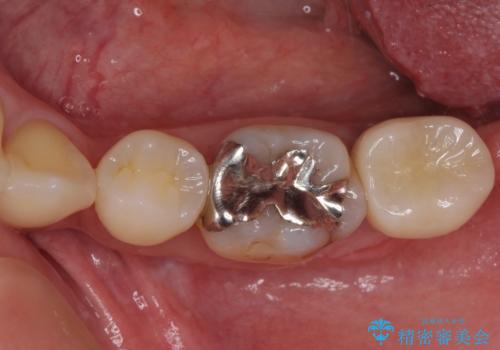

- 転倒により前歯3本が折れてしまったとのことで、インプラントによる治療を希望して来院された患者様です。

既に近医で真ん中の歯1本は抜歯されており、その隣の2本も破折していると言われたとのことでした。

診断をした結果、前医の診断の通り、2本とも破折しており、既に抜去している歯を含めて3本の抜歯が必要な状態でした。

抜歯する歯の両隣も治療が必要と思える歯であったため、広範囲なオールセラミックブリッジによる治療も提案しましたが、患者様本人の希望もあってインプラント2本による欠損部のみのブリッジ治療を行うこととしました。

歯の破折による抜歯のため、歯槽骨の欠損が大きく、骨造成処置の併用が必要であり、骨造成が落ち着くまでに半年ほど時間を要することになります。

2本同時に抜去して一時的な入れ歯の使用を提案しましたが、極力固定式の仮歯を使用したいとのことで、半年に1本ずつ埋入することとし、トータルで1年強を要する治療計画となりました。

治療により前歯は非常に安定しましたが、インプラント部の両隣、特に反対側の前歯はクラウンのやり直しが必要な状態であったので、今後反対側の治療も実施していく予定です。